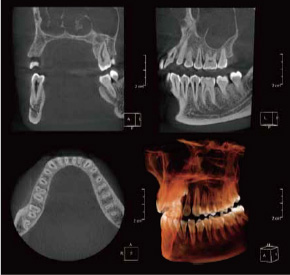

歯科用3Dパノラマ撮影装置(エクセラスマート F+)

当診療所では、歯科用3Dパノラマ撮影装置(エクセラスマート F+)を導入しております。

これまで以上に、より正確に患部の状態を把握できるようになり、患者様に精度の高い、安全で確実な歯科診療を提供することができるようになりました。

従来に比べ、より高画質で高精度の画像撮影が可能に。

歯根の形態から上顎洞・顎関節等に至るまで、総合的により細部の把握が可能になり、1枚の写真で的確な診断が容易にできるようになりました。